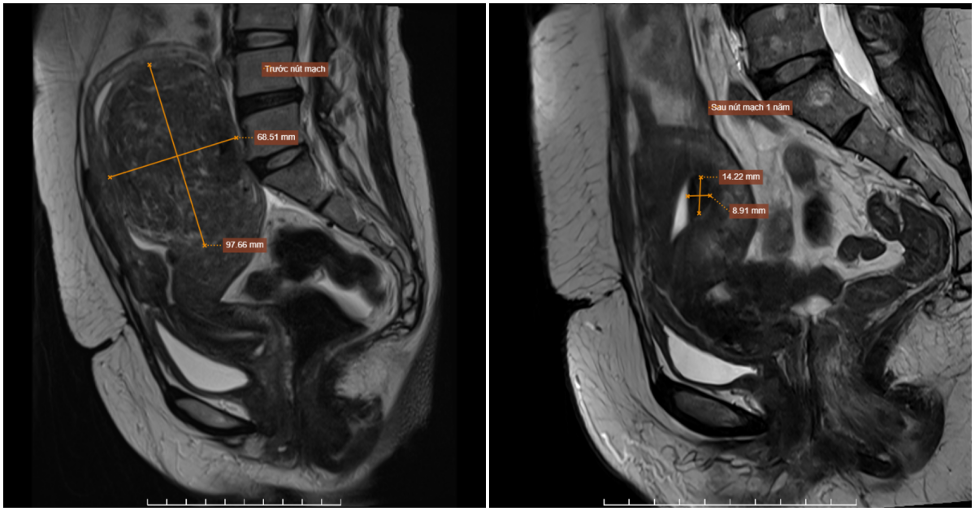

The fibroid's size changed before and after intervention. Photo: Tam Anh General Hospital

Two years ago, Ms. Lan discovered a uterine fibroid about 4 cm but did not seek treatment. Recently, experiencing prolonged menstrual irregularities, she visited Tam Anh General Hospital Hanoi. An MRI revealed the fibroid had grown to 9,7 x 6,8 cm, located within the uterine muscle layer, in the posterior fundus of the uterus, pushing the uterine lining inward. Doctors diagnosed the fibroid as highly vascularized, belonging to FIGO 2, a type prone to causing menorrhagia and severe menstrual pain.